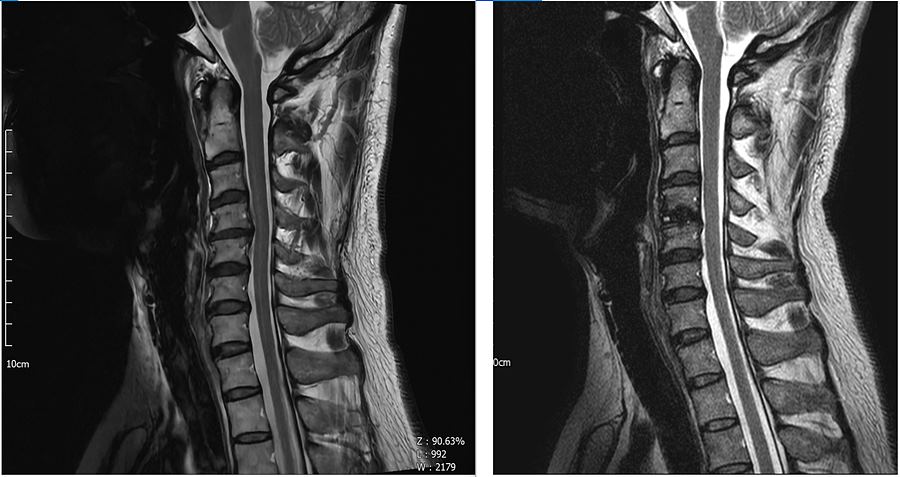

2. MRI 가로 사진 : 오른쪽이 수술후

. C4-C5 사이의 사진.

. 수술 후 디스크 있던 자리에 케이지가 보인다. (Zimmer Biomet Fidji Cervical 14/17/6mm)

. 가운데 척수가 한쪽으로 쏠렸었는데 수술후 약간이지만 가운데로 돌아왔고 공간도 생긴 것이 확인된다.

. 디스크를 모두 걷어내고 왼쪽 신경공을 넓혔지만 워낙 많이 막혀 있었기 때문에 반대편처럼 넓게까지는 안되는것 같다.

. 하지만 아래사진처럼 케이지를 박으면서 높이가 달라져서 그나마 괜찮은 것 같다.

. 오른쪽 신경공은 수술 전후 상관없이 넓다.